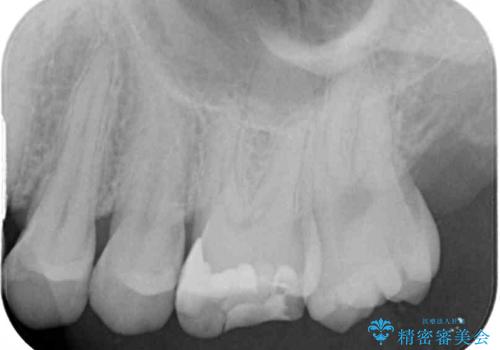

- 奥歯の詰め物が外れてしまったとのことで来院された患者様です。

幾度も詰め物治療を行ったため継ぎ接ぎだらけとなっていたため、インレーにて修復治療をすることとしました。

咬合力が強いため、ゴールド合金(PGA)のインレーを選択することとしました。

ゴールドインレーは銀歯のインレーやセラミックインレーと比べ、「技工操作の精度が高く、適合が著しく良い」というメリットがあります。特に上の奥歯は歯科医師の操作が行いにくいため、「適合の良さ」は再治療のリスクを防ぐ上でとても重要な要素となります。